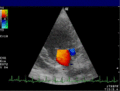

Die Aussagekraft der Sonografie kann erheblich durch die Anwendung des Doppler-Effekts erhöht werden. Man unterscheidet eindimensionale Verfahren (Pulsed-Wave-Doppler, Continuous-Wave-Doppler, auch als D-mode bezeichnet) von zweidimensionalen, farbkodierten Anwendungen (Farbdoppler – F-mode). Die Kombination B-Bild mit Pulsed-Wave-Doppler (PW-Doppler) nennt man auch Duplex.[4]

Doppler-Verfahren werden benutzt zur Bestimmung von Blutfluss-Geschwindigkeiten, zur Entdeckung und Beurteilung von Herz(klappen)fehlern, Verengungen (Stenosen), Verschlüssen oder Kurzschlussverbindungen (Shunts).

Bei der farbkodierten Doppler-Sonografie wird für einen großen Bereich eines konventionellen Ultraschallbildes (Color-Window) die örtliche Doppler-Frequenz (= mittlere Flussgeschwindigkeit) und deren Schwankungsbreite bestimmt. Damit möchte man die Turbulenz der Strömung abschätzen. Aufgrund der statistischen Bewegungen der Streuteilchen ist die Schwankungsbreite der Fließgeschwindigkeit jedoch stets größer als die Turbulenz. Das Ergebnis wird in Falschfarben auf dem B-Bild überlagert, also in Farbtönen von rot und blau für verschiedene Blutgeschwindigkeit und grün für Turbulenz. Hierbei steht üblicherweise die Farbe Rot für Bewegung auf den Schallkopf zu, während mit blauen Farbtönen Flüsse weg von der Sonde codiert werden. Bereiche der Geschwindigkeit 0 werden durch die Elektronik unterdrückt.

Anwendung des Doppler-Verfahrens bei einer Herzuntersuchung: Mitralklappeninsuffizienz -

Farb-Doppler und PW-Doppler. Innerhalb der Stenose ist wegen der hohen Flussgeschwindigkeit und des resultierenden Alias-Effekts die Geschwindigkeit in Blau kodiert. -